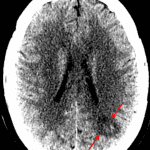

- Area of loss of gray-white differentiation in the left parietal lobe along the MCA/PCA watershed zone

- Hypodensity in the left caudate head

- Scattered subcortical and periventricular white matter hypodensities

- Intracranial atherosclerosis

- Acute left MCA/PCA and ACA/MCA watershed infarcts

- Acute left caudate head infarct

Area of loss of gray-white differentiation in the left parietal lobe along the MCA/PCA watershed zone concerning for acute ischemia. No evidence of hemorrhagic transformation or associated mass effect. Recommend brain MRI without contrast for further evaluation.

Age-indeterminate left caudate head infarct, which can also be further evaluated with MRI.

No acute hemorrhage or mass effect.